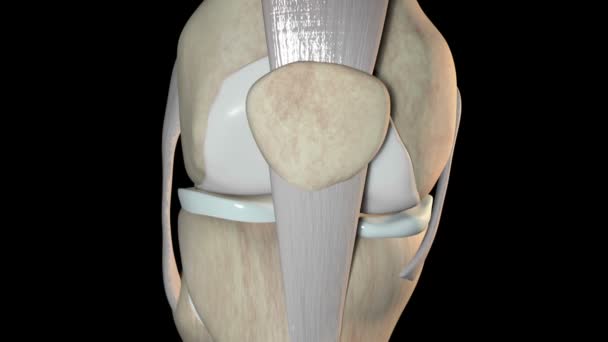

Надколенник располагается в толще сухожилия, разгибающего голень. Это сухожилие образовано слиянием четырех мышц передней поверхности бедра – так называемой четырехглавой мышцы. Снизу от надколенника начинается связка надколенника, которая крепится к передней части большеберцовой кости (к бугристости большеберцовой кости). Иногда связку надколенника называют собственной связкой надколенника. При разогнутой ноге надколенник как бы «плавает» над коленным суставом, располагаясь спереди и выше суставной щели. Но при сгибании в колене надколенник ложится в специальную выемку (борозду) между двумя мыщелками бедренной кости, и начинает работать как блок.

Изнутри надколенник покрыт толстым слоем хряща, который нужен для того, чтобы скользить по хрящу мыщелков бедренной кости. Хрящ надколенника – самый толстый у человека – его толщина может превышать 5 миллиметров! Естественно, он толстый не просто так, а потому, что надколенник испытывает очень сильные нагрузки. Подробнее об анатомии коленного сустава и надколенника в частности вы можете узнать на нашем сайте.

Надколенник имеет две поверхности — переднюю, которая непосредственно может быть прощупана через кожу; заднюю или суставную, которая скользит по бедренной кости.

На рисунке изображен надколенник — слева его передняя поверхность, которая пальпируется через кожу; справа — суставная поверхность, которая учавствует в образовании коленного сустава.